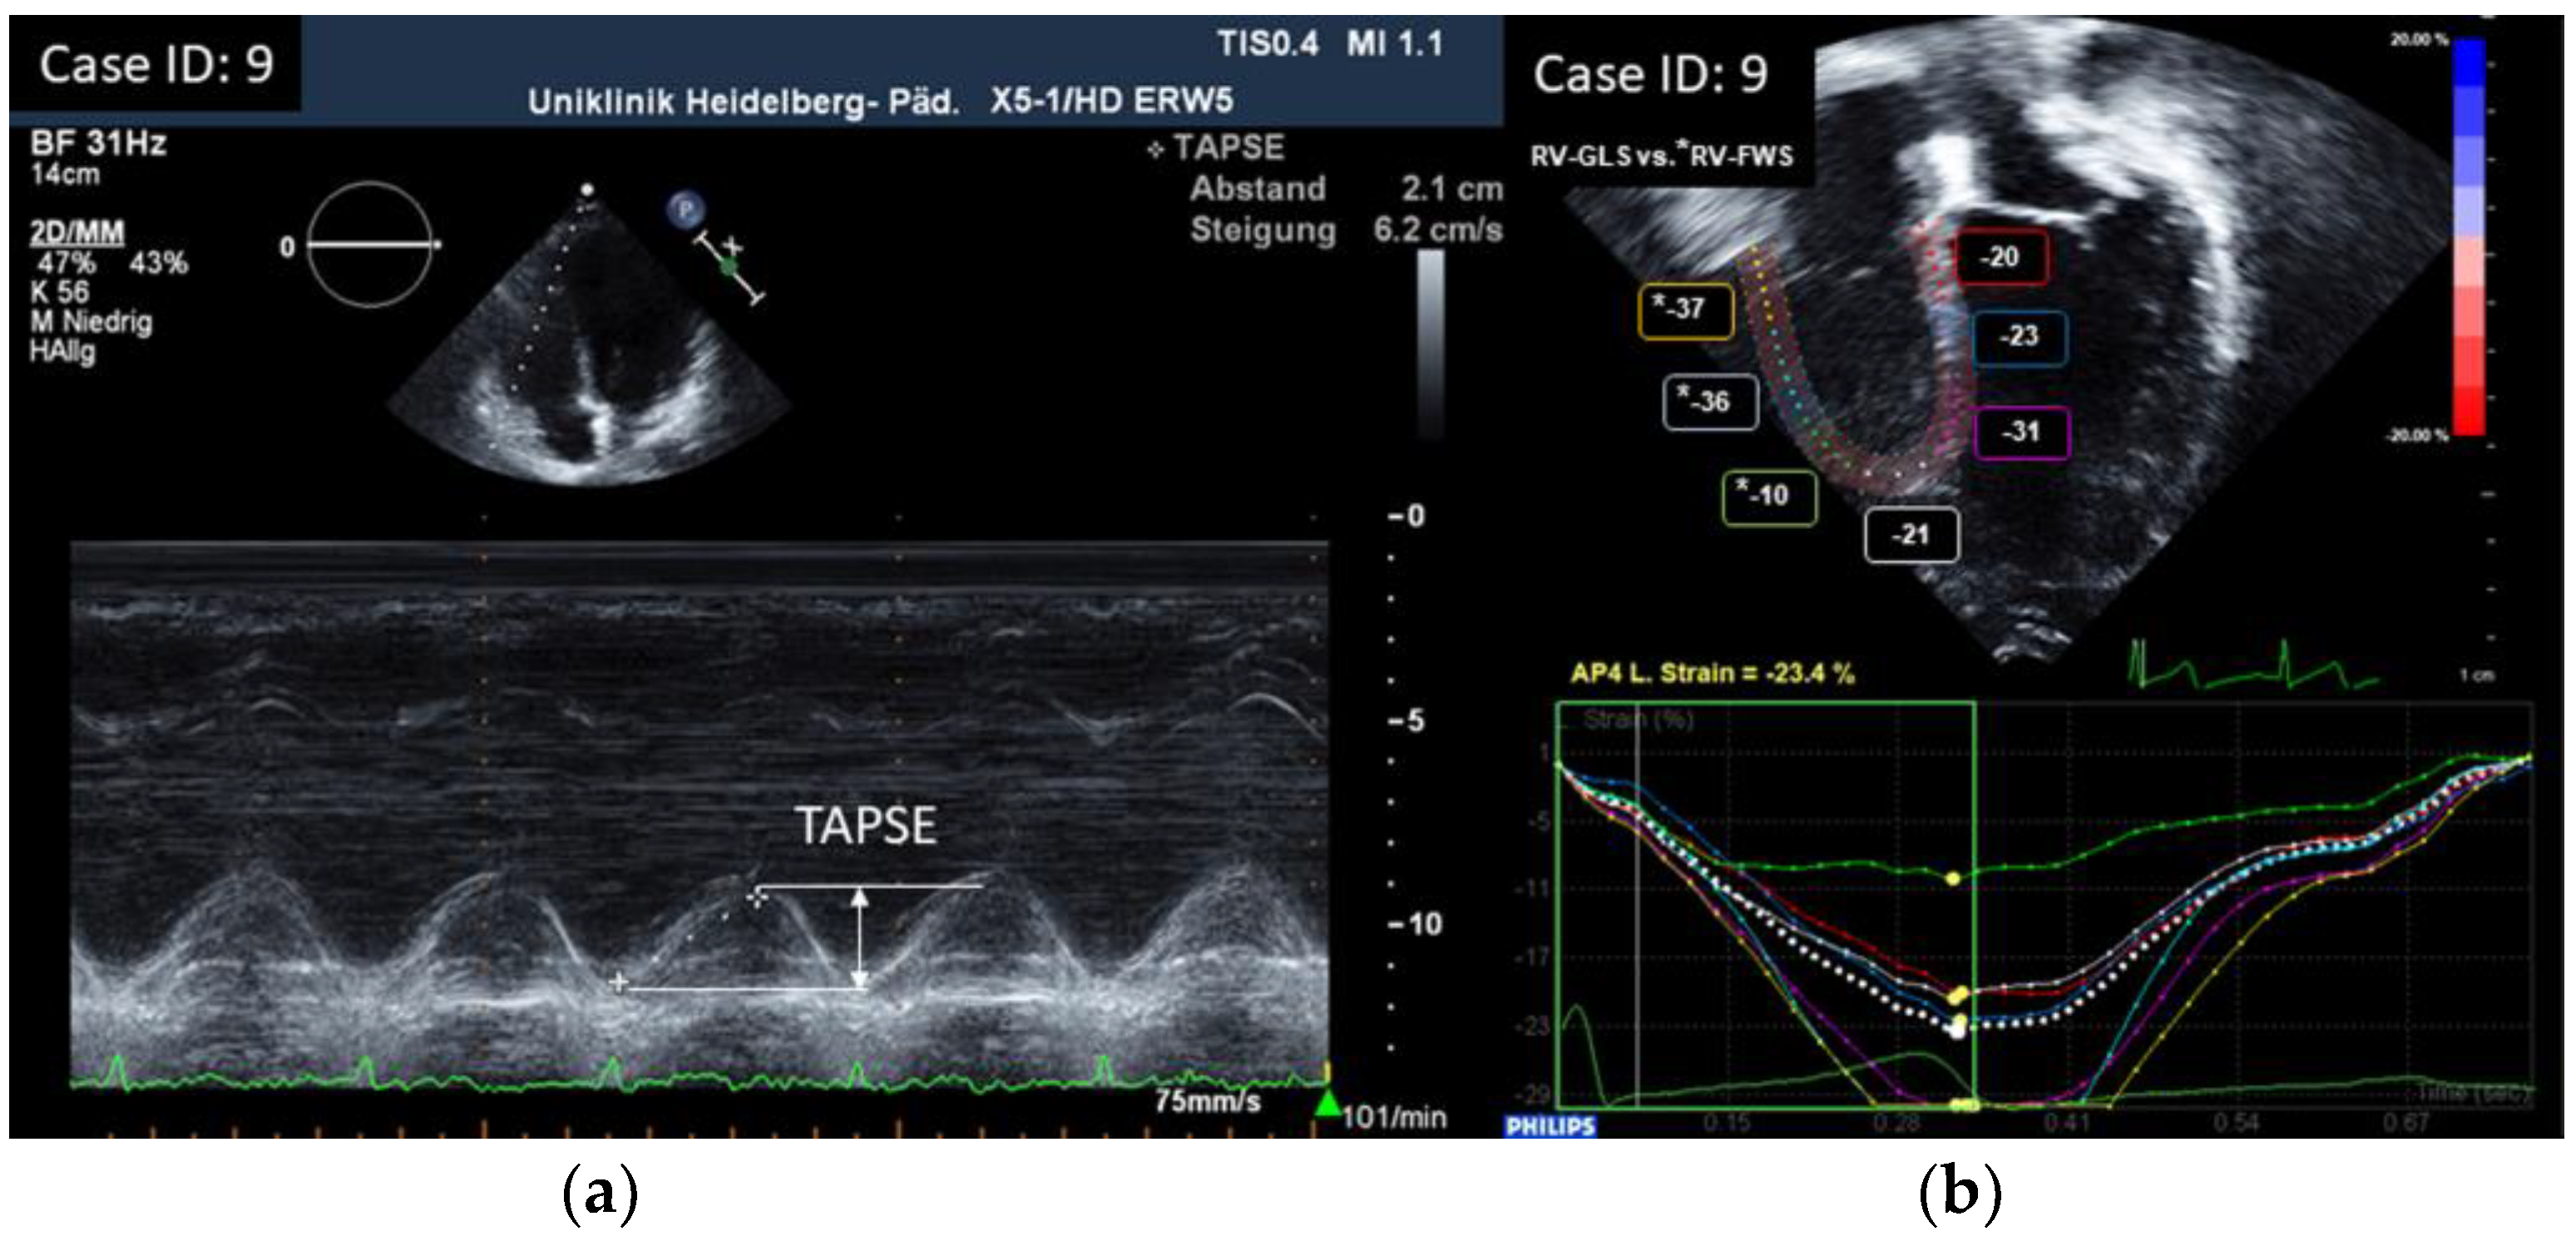

| (a) | |||||||

| ID | TAPSE cm | RV GLS % (ped.) | RV FWS % (adult) | TV S’ Vmaxcm/s | RV FAC % | RV-MPI | |

| 1 | 1.9 | −22.6 | / | 12.6 | 44.5 | 0.24 | |

| 2 | 1.7 | −25 | / | 12.1 | 43.1 | 0.23 | |

| 3 | 1.9 | −16.5 | / | 11.2 | 41.4 | 0.32 | |

| 4 | 2.7 | −11.6 | / | 12.4 | 48.6 | 0.31 | |

| 5 | 1.8 | −24.1 | / | 11.4 | 40.5 | 0.21 | |

| 6 | 1.8 | / | −23.3 | 11.5 | 43.0 | 0.38 | |

| 7 | 2 | −23.4 | / | 11.5 | 41.2 | 0.21 | |

| 8 | 1.9 | −22.9 | / | 15.3 | 40.6 | 0.21 | |

| 9 | 2.1 | / | −27.7 | 14.5 | 42.2 | 0.29 | |

| 10 | 1.9 | −20.9 | / | 17.5 | 49.0 | 0.36 | |

| 11 | 1.9 | −21 | / | 22.9 | 42.9 | 0.35 | |

| 12 | 2 | / | −22.7 | 13.2 | 42.3 | 0.27 | |

| 13 | 2 | / | −22.3 | 10.4 | 39.3 | 0.43 | |

| 14 | 1.5 | −23.6 | / | 8.44 | 47.0 | 0.33 | |

| 15 | 1.7 | / | −22.3 | 8.4 | 37.4 | 0.21 | |

| 16 | 2.3 | / | −28.0 | 14.3 | 40.2 | 0.26 | |

| 17 | 2.14 | −25.2 | / | 13.7 | 40.5 | 0.28 | |

| 18 | 2.1 | −22.3 | / | 9.8 | 34.0 | 0.24 | |